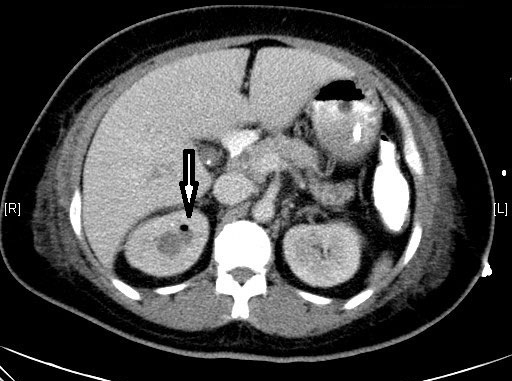

Prompt recognition and treatment crucial in pyelonephritis

Acute pyelonephritis is a bacterial infection of the kidney parenchyma that can cause organ damage and be life-threatening. It is associated with systemic symptoms and flank pain which are not usually present in lower urinary tract infections. Early recognition and aggressive management of sepsis is required to prevent serious complications. Patients should be urgently referred to the emergency department if they are unwell and showing signs of sepsis (hypotension, tachycardia, hypothermia or pyrexia, signs of systemic illness such as rigors). Patients at higher risk of severe disease (elderly comorbid patients or those in other risk groups) may also warrant urgent referral.